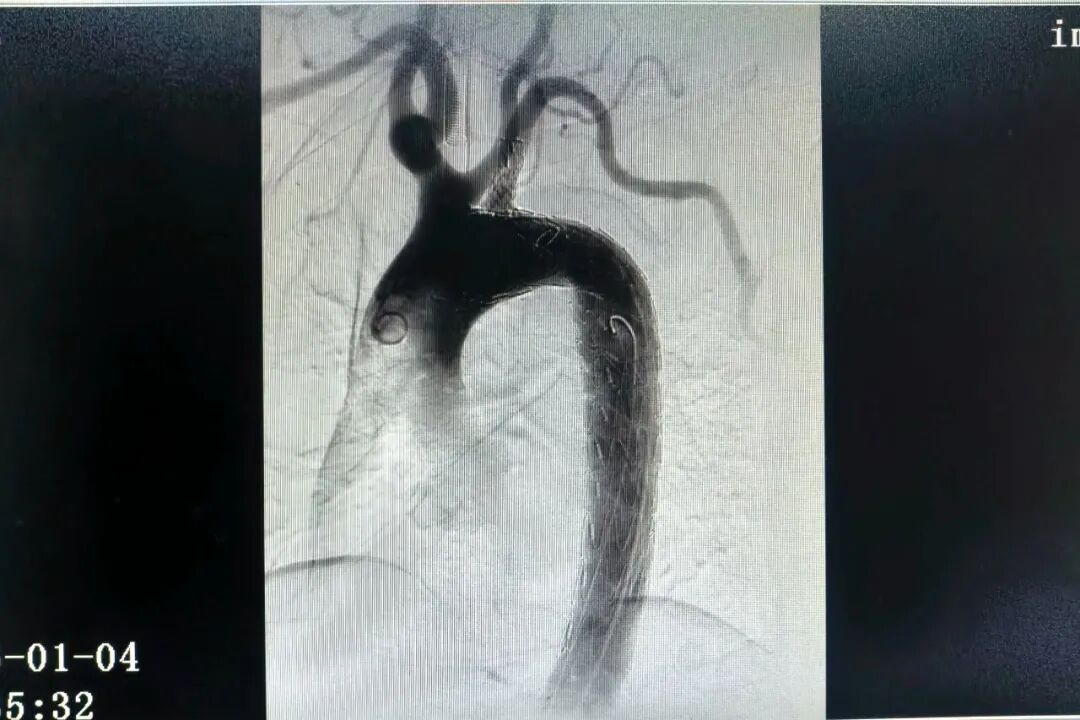

图片

(术后主动脉造影)

患者病情危急、进展迅猛,心血管内科团队第一时间组织多学科讨论,综合其年龄、基础疾病与病情特点,全面评估手术风险后,最终决定采用胸主动脉覆膜支架腔内隔绝术联合左锁骨下动脉覆膜支架植入术的微创治疗方案。经过周密的术前准备,心血管内科团队为患者施行手术,术中精准释放覆膜支架,成功重建血流通路。术后造影显示,胸主动脉支架与左锁骨下动脉分支支架扩张充分,贴壁良好,未见夹层及内漏,远端血流良好,手术达到预期效果。整台手术历时约两小时,术后患者安全返回病房。